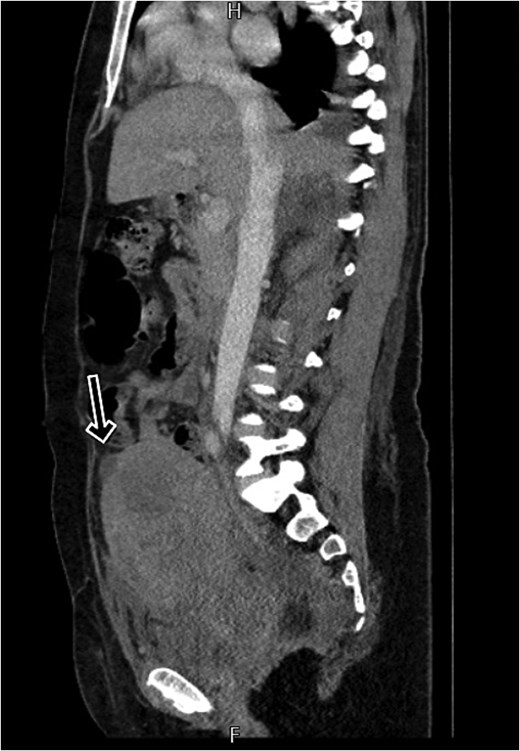

By postpartum day five, the patient exhibited persistent fever and worsening clinical status, unresponsive to broad-spectrum antibiotics. A contrast-enhanced computed tomography (CT) scan was performed, revealing a ruptured uterine scar with omental herniation and a large intra-abdominal abscess (Figs 1 and 2).

CT scan shows a linear small defect in the anterior wall of uterine fundus with small collection (2 × 1 cm).

CT scan revealing a ruptured uterine scar with omental herniation.